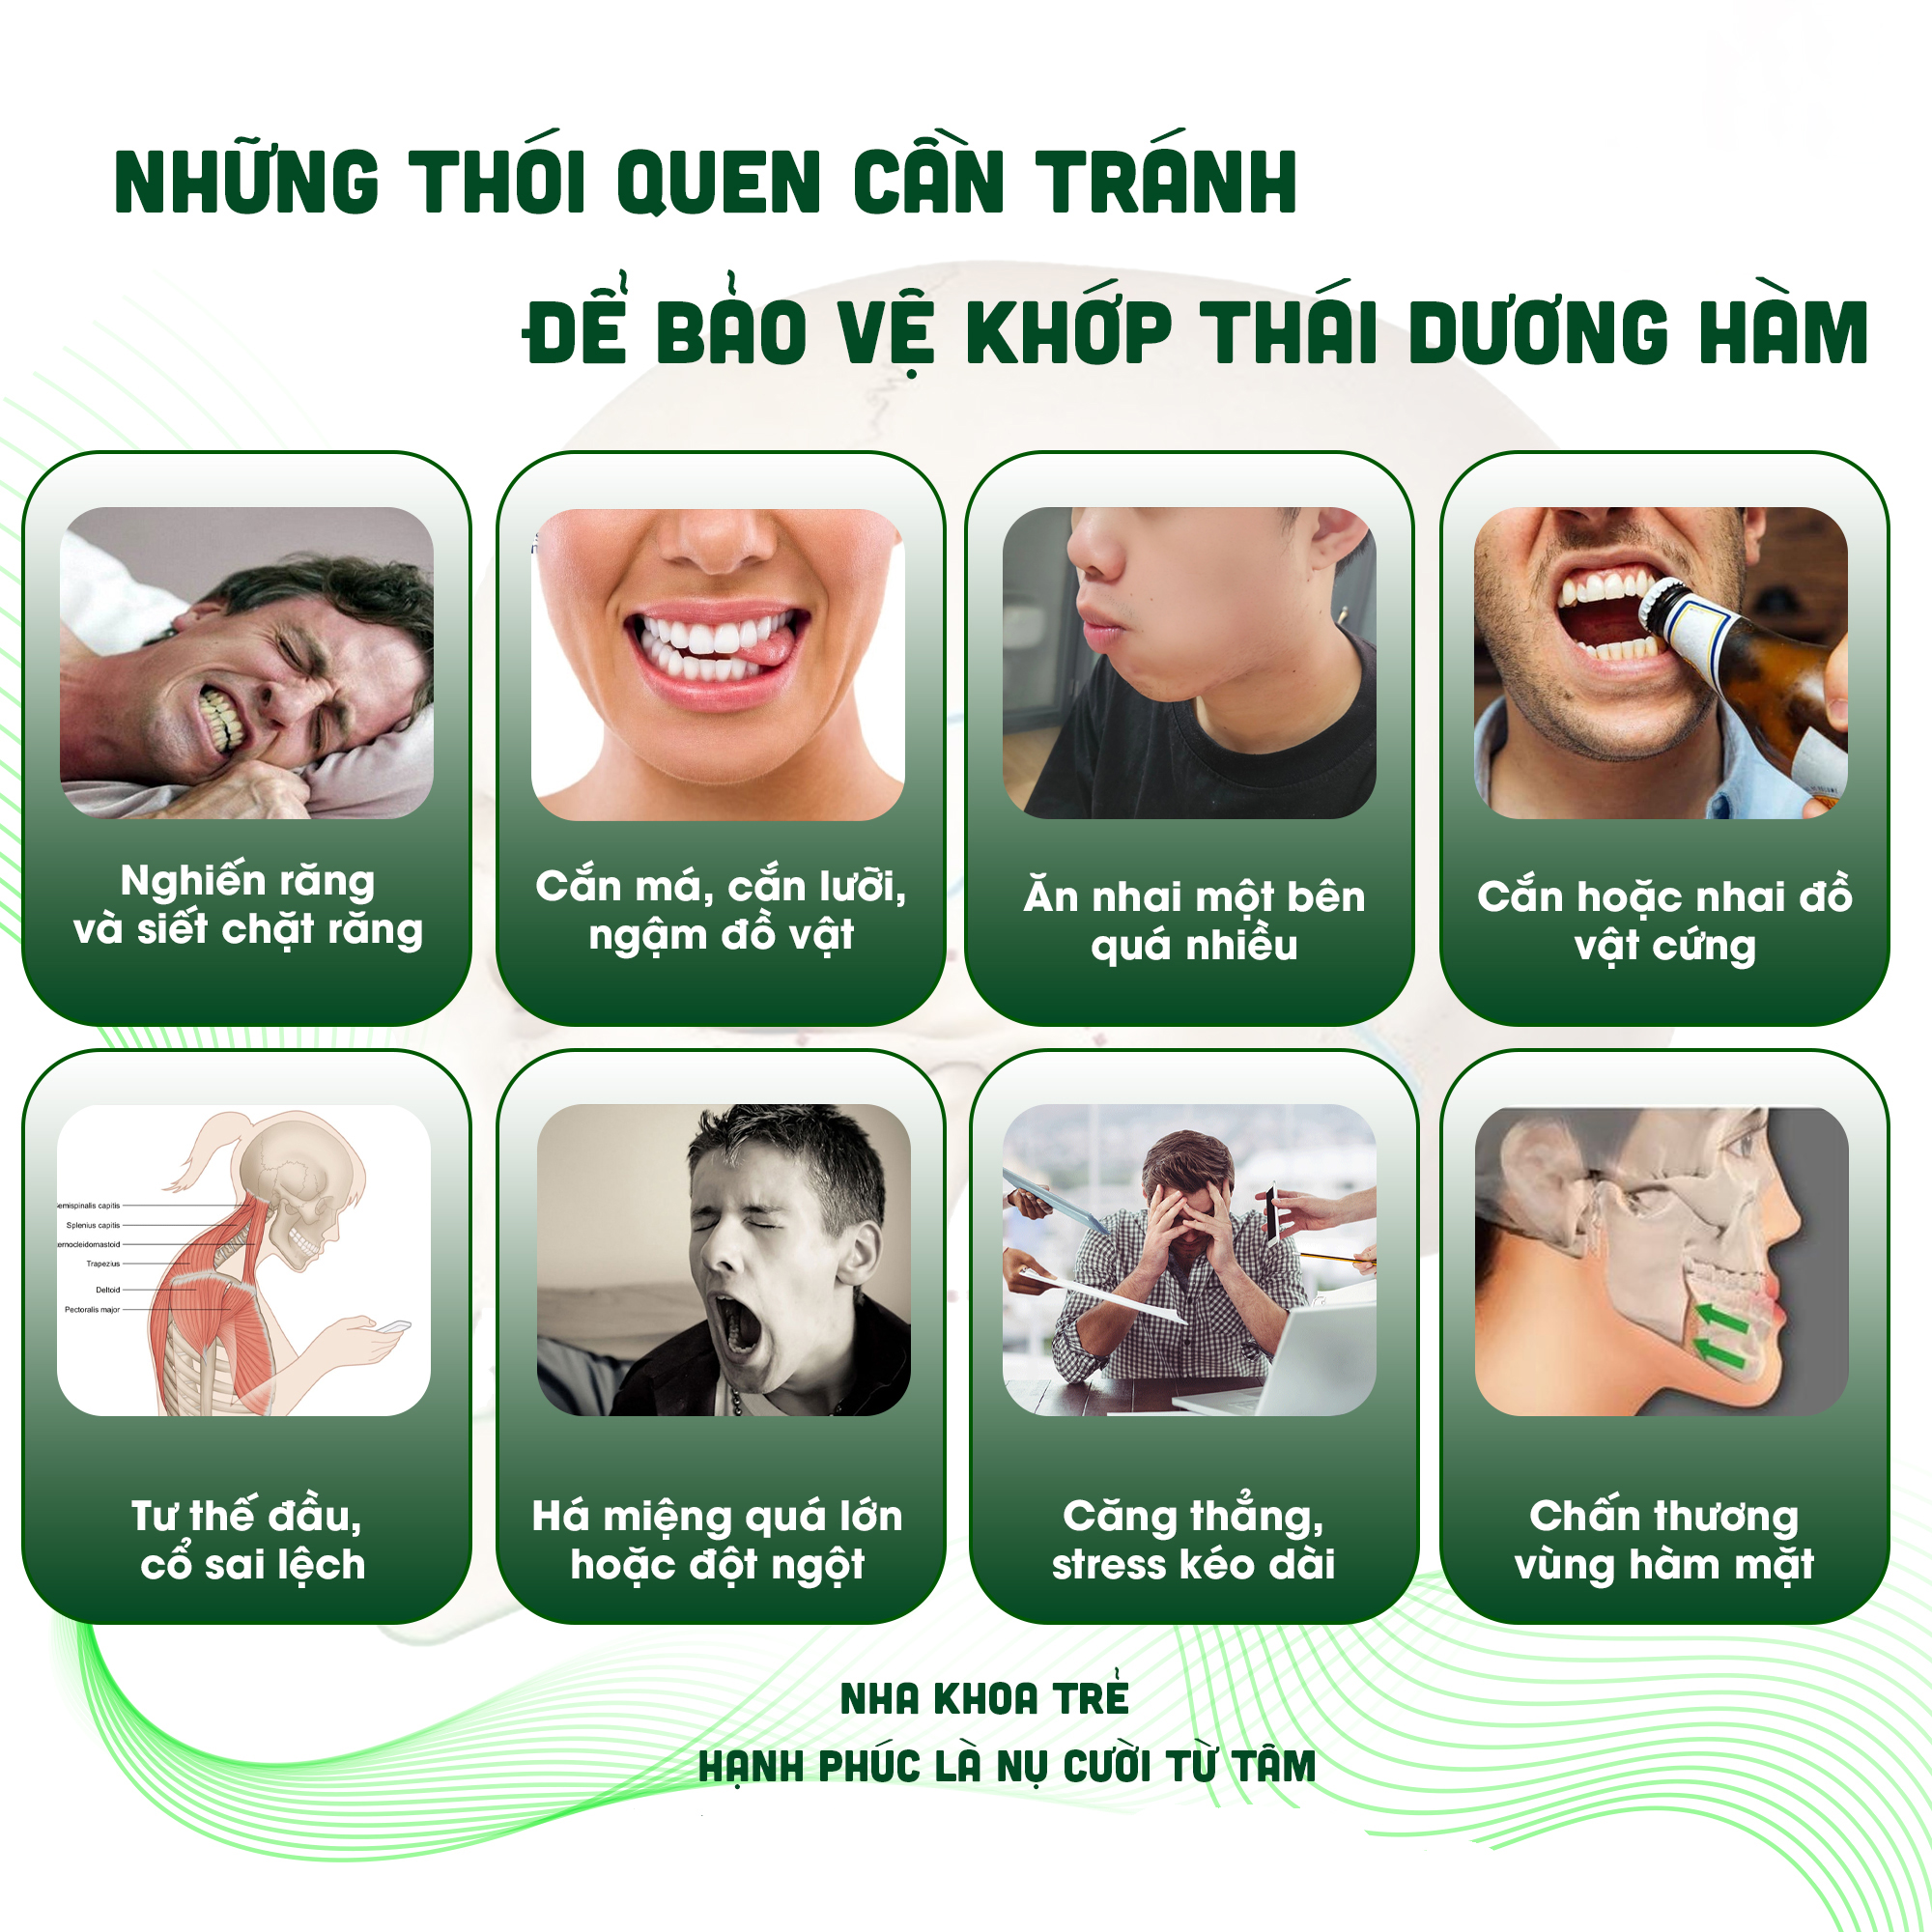

Những thói quen có thể gây ra hoặc làm nặng tình trạng loạn năng khớp thái dương hàm (TMD)